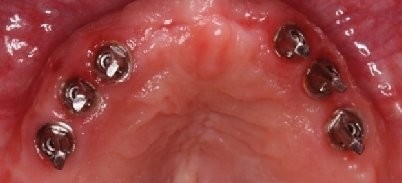

Der Herstellungsprozess soll nachfolgend anhand einer Stegversorgung mit dem Compartis ISUS dokumentiert werden. Nach der Freilegung der Implantate (Abb. 3) erfolgt im nächsten Termin in gewohnter Weise die Abformung mit einem Abformmaterial, das durch eine hohe Endhärte eine sichere Fixierung der Abformpfosten gewährleistet (z.B. Impregum, 3M ESPE, oder Monopren transfer, Kettenbach Dental) (Abb. 4).